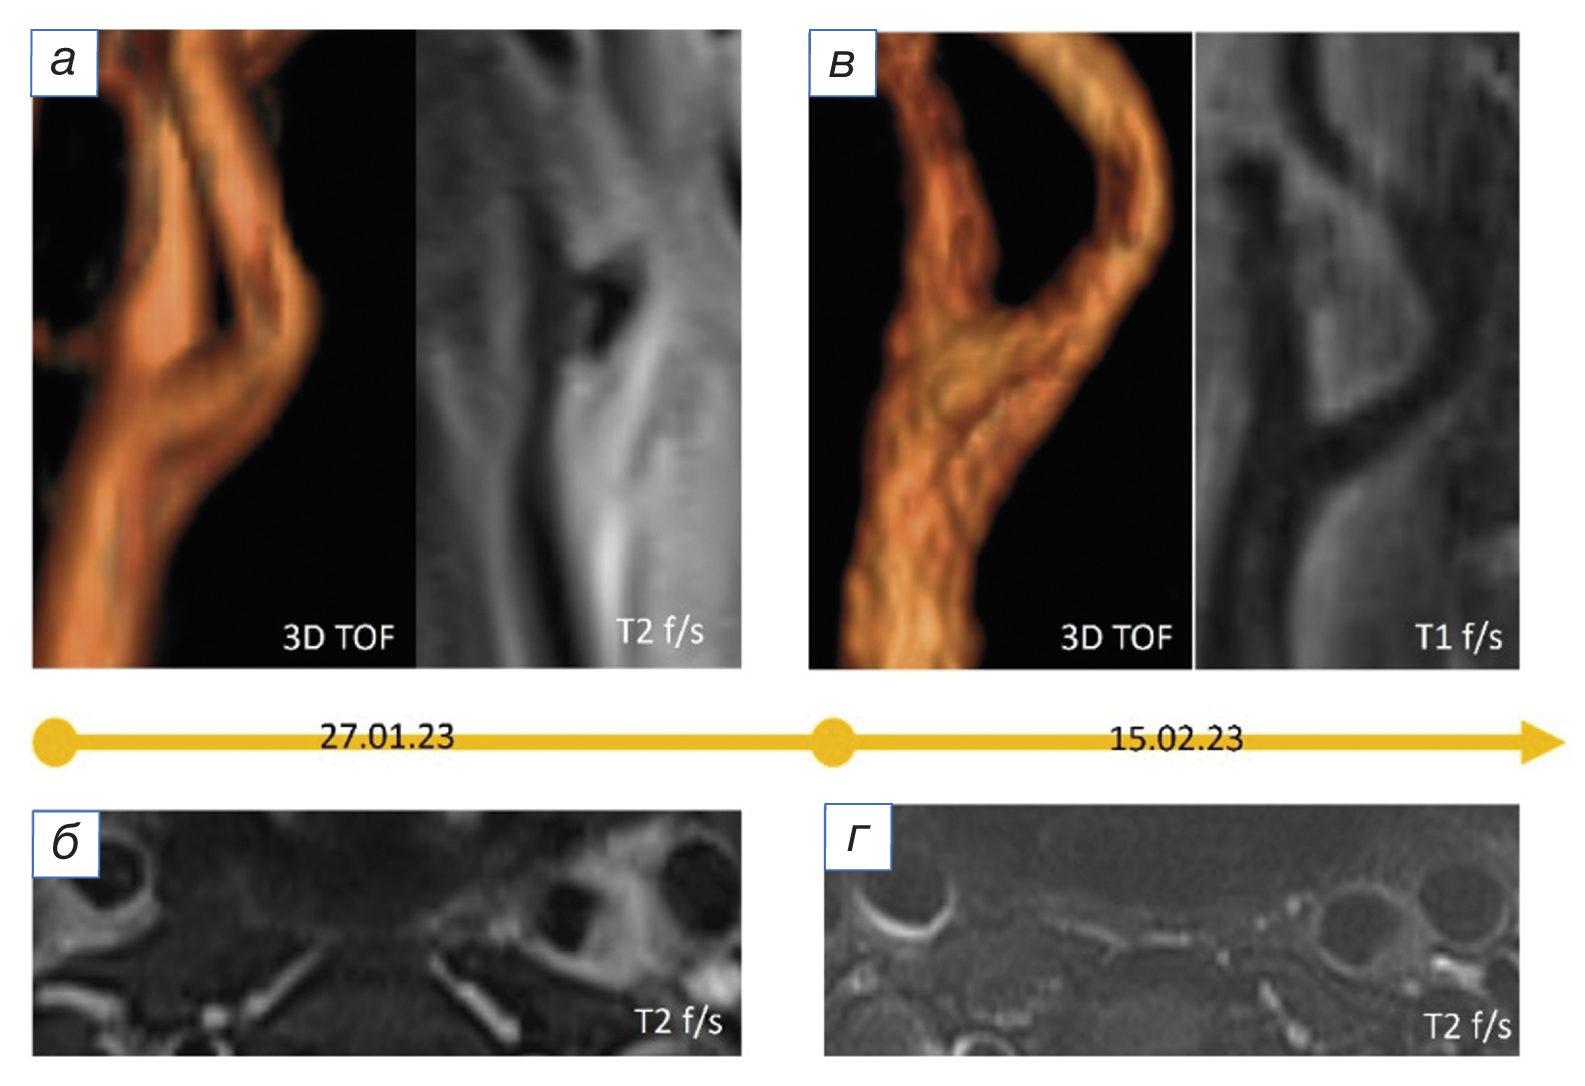

При ретроспективной оценке данных магнитно-резонансной томографии (МРТ) артерий шеи от 27.01.2023 в области бифуркации левой общей сонной артерии визуализировалась периваскулярная, эксцентрично расположенная зона изменённого МР-сигнала без чётких контуров, повышенной интенсивности в Т2 fat-sat (рис. 1 б, г), изоинтенсивная в Т2 (рис. 1 д), изо-/слабогиперинтенсивного сигнала в Т1 fat-sat (рис. 1 е), соответствующая периваскулярному воспалению; наружный контур артерии на этом уровне визуализировался нечётко. При МР-ангиографии (рис. 1 а, в) отмечалось гемодинамически незначимое сужение просвета артерии на этом уровне (рис. 1).

Рис. 1. Результаты магнитно-резонансной томографии шеи пациентки с TIPIC-синдромом в острый период: а, в (3D-TOF-ангиография) — локальное гемодинамически незначимое сужение просвета левой общей сонной артерии (белые стрелки); б, г (Т2 fat-sat), д (Т2), е (Т1 fat-sat) — периваскулярная, эксцентрично расположенная зона изменённого сигнала на уровне бифуркации левой общей сонной артерии (на периваскулярный инфильтрат указывают белые стрелки, красный контур).

Fig. 1. Results of magnetic resonance imaging of the neck of a patient with TIPIC syndrome in the acute period: а, в (3D-TOF-angiography) — local haemodynamically insignificant narrowing of the left common carotid artery lumen (white arrows); б, г (T2 fat-sat), д (T2), е (T1 fat-sat) — perivascular, eccentrically located zone of altered signal at the level of the left common carotid artery bifurcation (perivascular infiltrate is indicated by white arrows, red contour).

При поступлении по результатам МРТ-исследования от 15.02.2023 отмечалось увеличение внутреннего просвета артерии, уменьшение зоны периваскулярных изменений и выраженности отёка; наружный контур артерии стал более чётким (рис. 2). Использование контрастного усиления позволило более чётко визуализировать зону периваскулярного воспаления (рис. 3 д) в сравнении с нативным исследованием (рис. 3 б).

Рис. 2. Результаты магнитно-резонансной томографии шеи пациентки с TIPIC-синдромом в динамике: острый период (а, б) и контрольное исследование через 2,5 недели (в, г). Отмечается уменьшение зоны периваскулярного инфильтрата, увеличение просвета артерии; наружный контур артерии стал более чётким.

Fig. 2. Results of magnetic resonance imaging of the neck of a patient with TIPIC syndrome in dynamics: acute period (а, б) and the control study after 2.5 weeks (в, г). The perivascular infiltrate zone is decreased, the arterial lumen is increased; the external contour of the artery has become clearer.